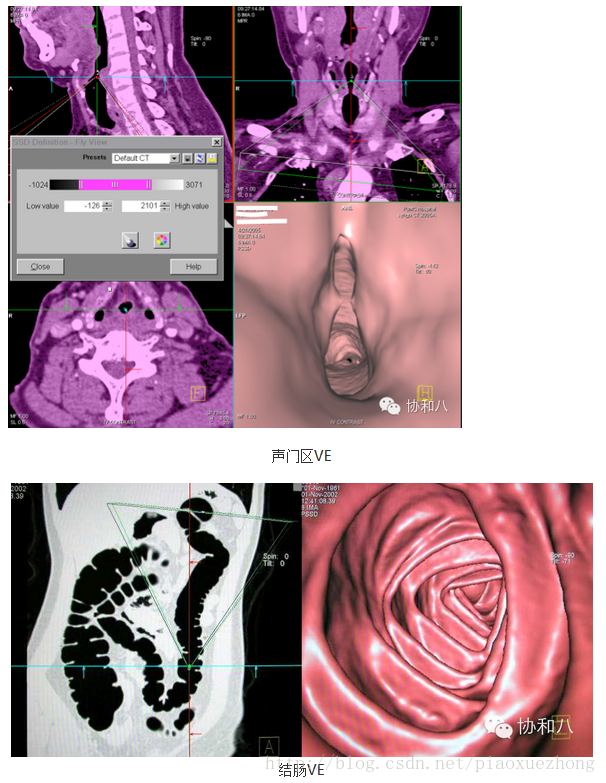

虚拟内镜技术(VE)

这种CT重建图像可以模拟各种内镜检查的效果,它是假设视线位于索要观察的管“腔”内,通过设定一系列的参数范围,即可看到管“腔”内的结构: